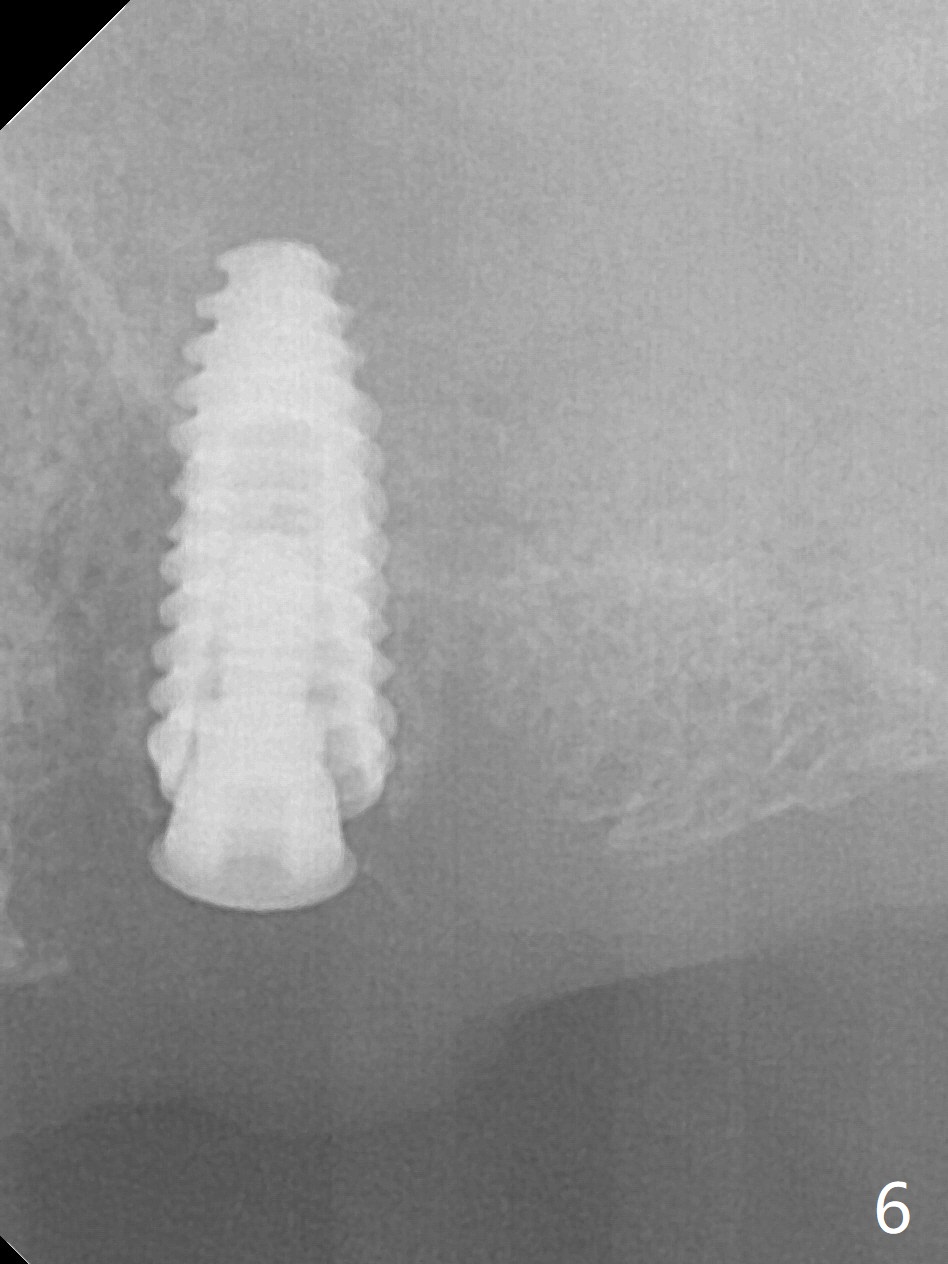

After a 4x10 mm implant is placed with fixture mounting (Fig.2 M) following sinus lift (*) at #12, osteotomy is initiated at #10 (Fig.1 (T: tube of surgical guide)). It appears that the drill (D) has good trajectory (between the Incisive Canal (red dashed line) and the canine root). The final position of the implant at #10 is acceptable (Fig.3). The implant at #12 is placed deeper (Fig.4 (arrow), as compared to Fig.2) because of clinically buccal superficial placement. The most critical challenge is anterior deep bite associated with posterior collapse. Periodontal dressing is applied. When the latter dislodges, there is minimal clearance for a provisional. Periodontal dressing is re-applied. The patient (smoker, partial edentulism with occlusal interference) returns for provisional nearly 1 month postop with chief complaint "something is lost in the back". In fact the healing abutment at #12 is lost with buccal granulation tissue (Fig.5). When a new abutment is seated, there is discomfort. When a healing screw is placed, it cannot be seated completely with two separate trials (Fig.6,7). Should we leave it as it is or open up for complete seating? It appears that the implant is loose. After preparation for clearance at #10, the abutment is retightened. It appears to turn with the underlying implant with discomfort. A 4x5 mm healing abutment is placed to reduce micro-movement. One week later, the infection at #12 dissolves with oral Amoxicillin (Fig.8). Due to limited occlusal clearance and implant tenderness when the abutment abutment is retightened, the cemented abutment is changed to a healing abutment. The implant at #10 seems to be osteointegrated, while the healing screw at #12 remains incomplete seating 3 months postop (Fig.9). The loose healing screw cannot be retightened securely, as there is bone loss around the implant 3 months postop (Fig.10 *). When a 4.5 mm x 15 degree 4 mm cuff angled abutment is placed, the mesiodistal trajectory improves (Fig.11), but there is no occlusal clearance (Fig.12). The latter would form when posterior support is established (Fig.13, either removable appliance (which the patient hates) or fixed one (finance)). Fig.14 shows the unhealed site of #12. Incision confirms the bone loss around the implant, which is removed. Although the sinus floor is absent, there is no membrane perforation. After debridement, allograft mixed with small amount of Osteogen is placed (Fig.15,16 G) and covered with Osteogen plug and 6-month membrane.